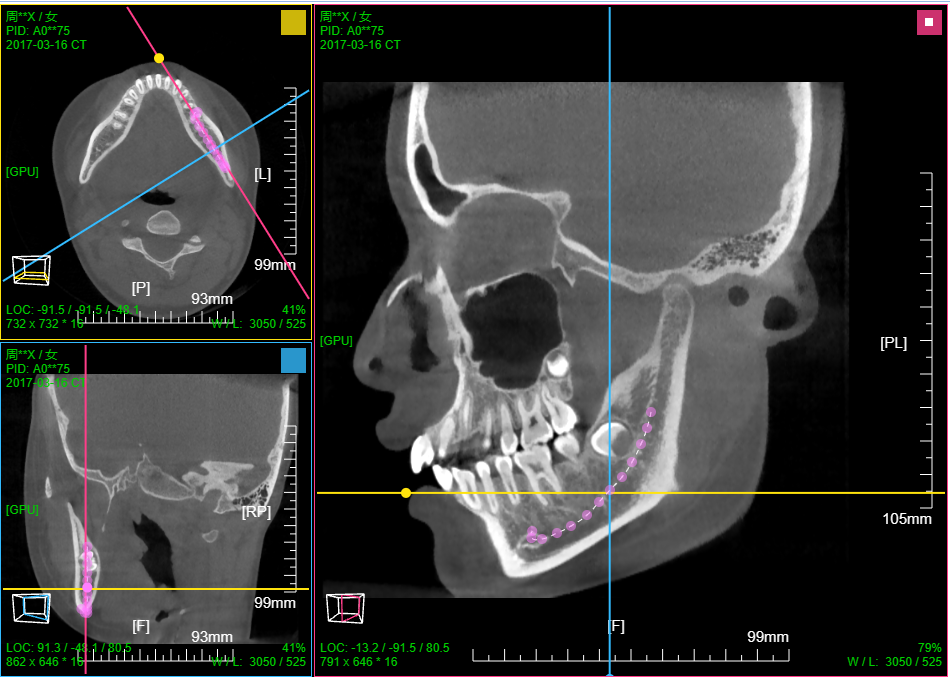

九、牙神经管标记

打开CBCT图像; 菜单 选择 "路径点手工标记"

MPR调整到合适的位置,显示处神经管,点击进行神经管标记

进入三维渲染模式(MIP或VR),然后点击菜单 ”神经管渲染显示“

也见视频操作录像 牙神经管标记